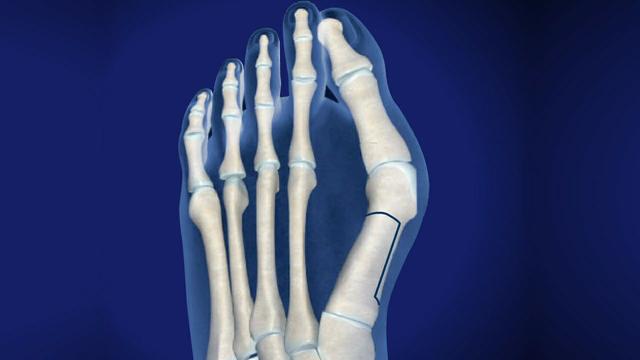

科普_-大脚趾骨痛-大脚趾骨痛一